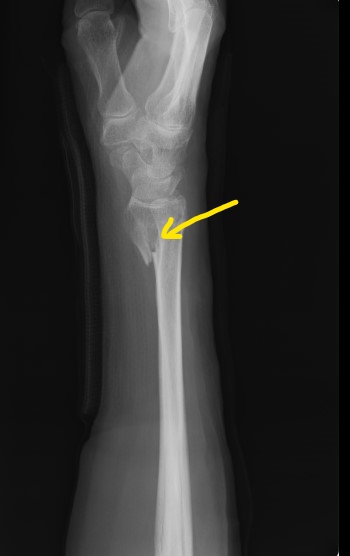

〇右前腕骨骨折(スミス骨折)

自転車で転倒し手をつき手首を骨折しました。

病院でレントゲン検査の結果、3か所の骨折が認められました。

後日手術の予定が組まれ,全身麻酔下で行うことを聞かされた時に非常に困惑し、セカンドオピニオンとして手の専門外科に相談に行かれました。

ここでも手術療法が妥当だと日程を組むことになってしまいました。

手術をしないで治ることはできないかとインターネットで調べ当院を知り相談に来られました。

今回事情を聴き、整形外科の先生と相談をし当院で処置と経過観察をすることになりました。

整骨院の従来の固定法である副木(シャーレ)と包帯を駆使して患者さんに負担の少ない固定をしました。

毎日 固定具を外し患部の浮腫の除去、血行維持、清拭、超音波治療を行います。固定具に不自由があれば

修正をしました。 このように毎日患者さんに触れ、不安を聞くことにより自律神経も安定し良い結果につながるのです。

経過は非常に良好で転移(骨のずれ)もなく約2か月で薬剤師の仕事に復帰されました。